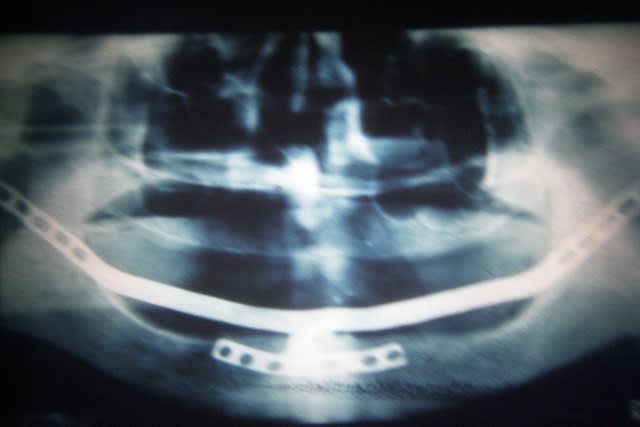

Tu sais, pxav, la basale est bien plus normée que ces drôles de cadres ramiques ou autres implants ramiques...

Alors c est rigolo de voir cette pano de cadre ramique que certains trouvent presque normale alors que qd les praticiens voient des cas de basale ils nous sautent à la gorge sans réfléchir et presque comme si c était un réflexe conditionné

y a plus beaucoup d'os

y n'a plus qu'il n'y parait